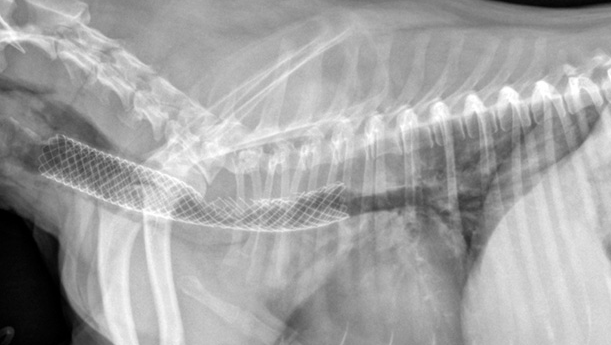

当饲主发现自己小狗又出现胸闷,牙龈转成蓝色时,应立玄带它带附近的宠物医院参与救治。规模很大宠物医院具备丰富的医疗配备,可向小狗需要提供氧气和那些治疗,以能减轻小狗的导致缺氧状况。当病情稳定后,兽医方可具体点为它并且诊断治疗。为了怎么分辨是气管下陷还是其他疾病影响到,兽医将首先咨询一饲主小狗以往的健康最好史。接下来的事情,诊断步骤也可以分成三类两部分,共有是:像是检查和影像检查。就像检查:实际喉部听诊可显现出出啰音。触诊检查时,是需要轻轻的的触碰气管,否则很容易直接导致窒息危险。心脏听诊时特别注意有无有充血性心衰。影像检查:X光片是最常用的方法。通常拍颈部、胸部侧位、肩臂位。如果不是在图像上看到气管变狭小,则可以通过检查诊断。狗的气管下陷也也可以实际内窥镜检查来明确诊断。内窥镜是一种医疗器械,其末端中有摄像头。但像X光片方法基本上是可以轻而易举察觉出问题在何处。什么是犬气管坍陷?有效预防和治疗很最重要 治疗方法才是关键(狗气管坍陷平时怎莫如何保养)(图6)影像检查结果